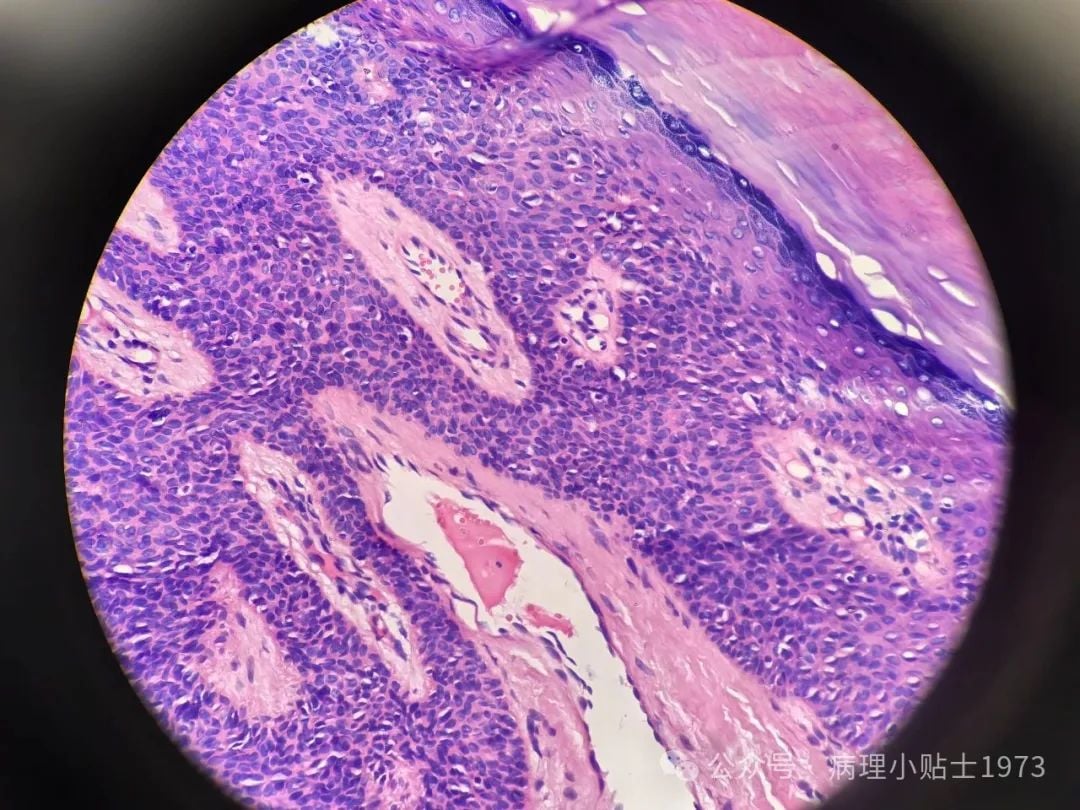

- 镜下观察: 在显微镜下,可以看到肿瘤由形态温和、大小一致的细胞构成,并形成了类似汗腺导管的结构。细胞没有明显的恶性特征,如异型性和快速分裂,这进一步证实了其良性性质。